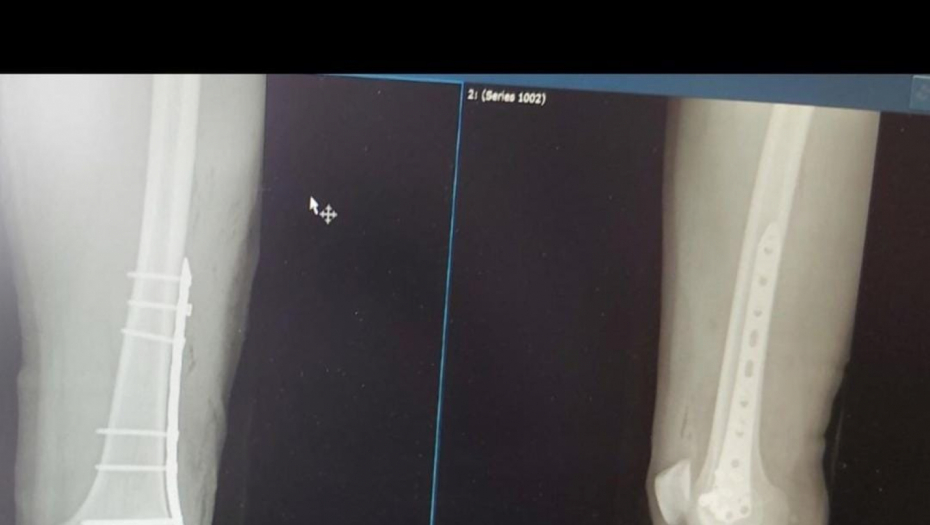

Bilal Brajlović imao je operaciju butne kosti na Institutu za ortopediju Banjica, gde je boravio prethodnih nekoliko dana, a o njemu su brigu vodili najveći stručnjaci iz te medicinske oblasti.

Brajlović se sada oglasio na svom Instagram nalogu i tom prilikom podelio fotografije na kojim se vidi da na dva mesta ima šavove i rane od operacije.

Iako deluje bolno, Bilal deluje lepo raspoloženo i nada se brzom oporavku a u opisu ove fotografije noge napisao je:

- Vratiću se jači - pisalo je u opisu fotografija noge.